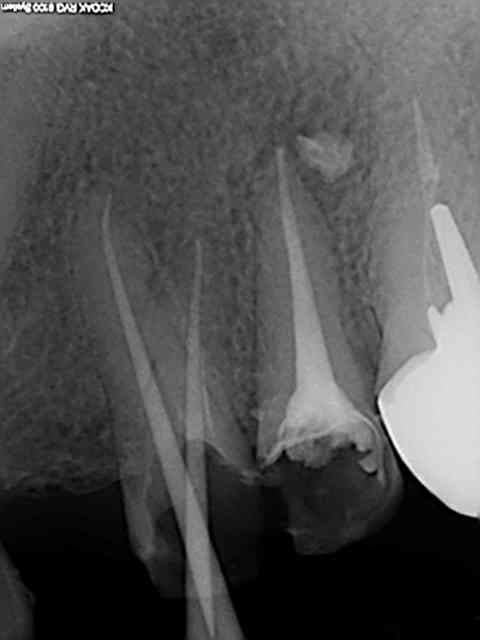

Tiens les endos de la semaine, que d'apex défoncés !-))

La 47 en fin le distal est obturé au système B (bouchon apical) et au mac spaden pour la partie coronaire, tu vois la différence à la radio ? Alors l'apex défoncé il faut avoir l'oeil ! peut etre mais à 25 centièmes et à conicité 6 %........-))